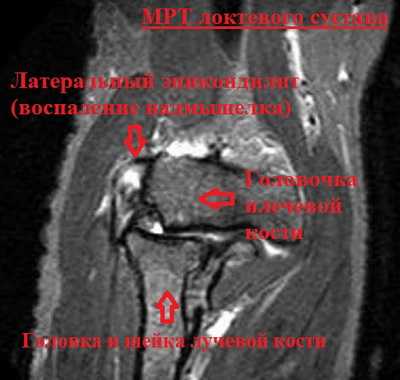

Рентгенологические изменения в локтевом суставе обычно отсутствуют. Хотя иногда возможно увидеть кальцификаты в области прикрепления сухожилий мышц-разгибателей к латеральному надмыщелку. Магнитно-резонансная томография может стать источником информации о внутрисуставной патологии, наличии сопутствующих повреждений хряща и связок локтевого сустава.

- Магнитно-резонансная томография (МРТ). Если доктор посчитает, что ваша проблема может быть связана с шейным отделом позвоночника, он может назначить МРТ. Этот метод обеспечивает хорошую визуализацию мягких тканей и используется для диагностики грыж межпозвонковых дисков и остеоартрита суставов шейного отдела позвоночника. И то, и другое состояние может проявляться болевым синдромом в руке.